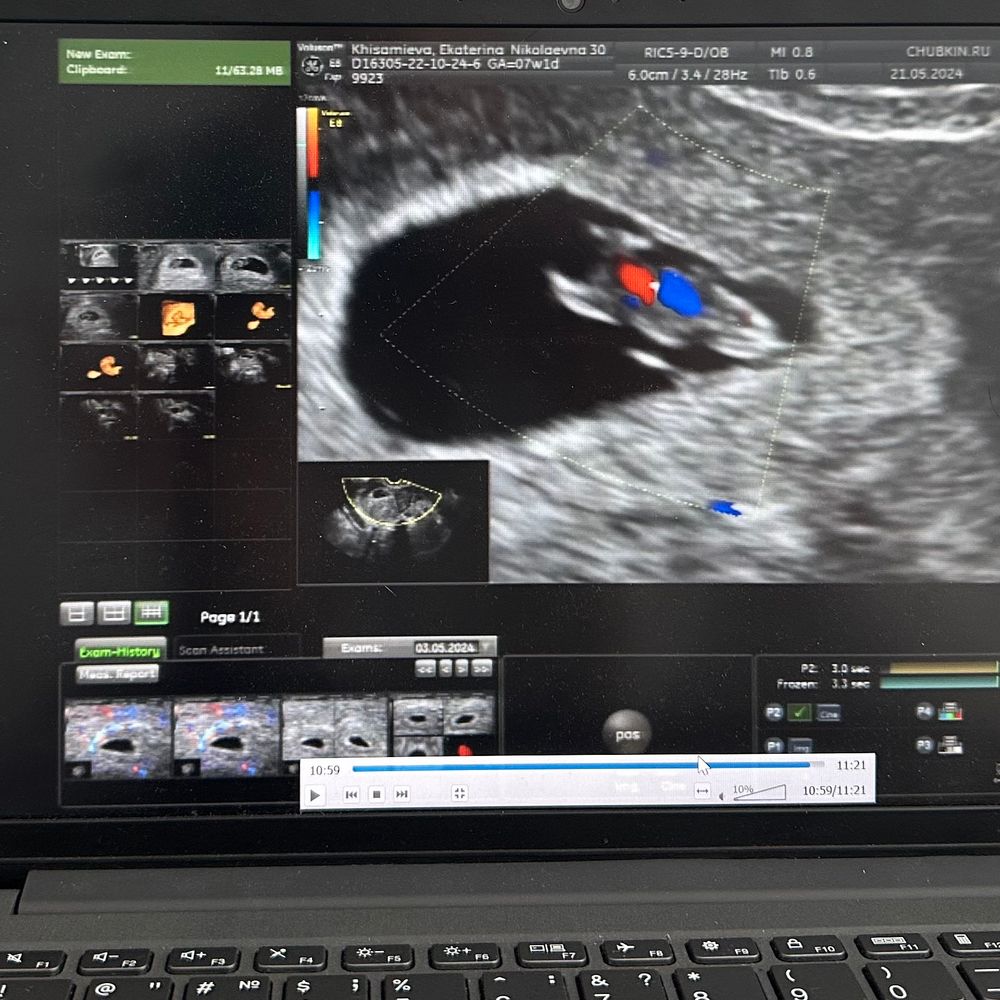

Результаты УЗИКТР 10.9, СБ 144 ❤️. Такой вот малышок (вчера делала УЗИ) 🫶. Соответствуем сроку, ручки, ножки формируются, 2 полушария в мозге, позвоночник. 4Д УЗИ.

Узи суперское, а что за аппарат узи такой, я тоже хочу 4 д узи)

Еся, я просто люблю ходить к конкретному врачу, он делает и 4д, видео после узи присылает ⭐️.